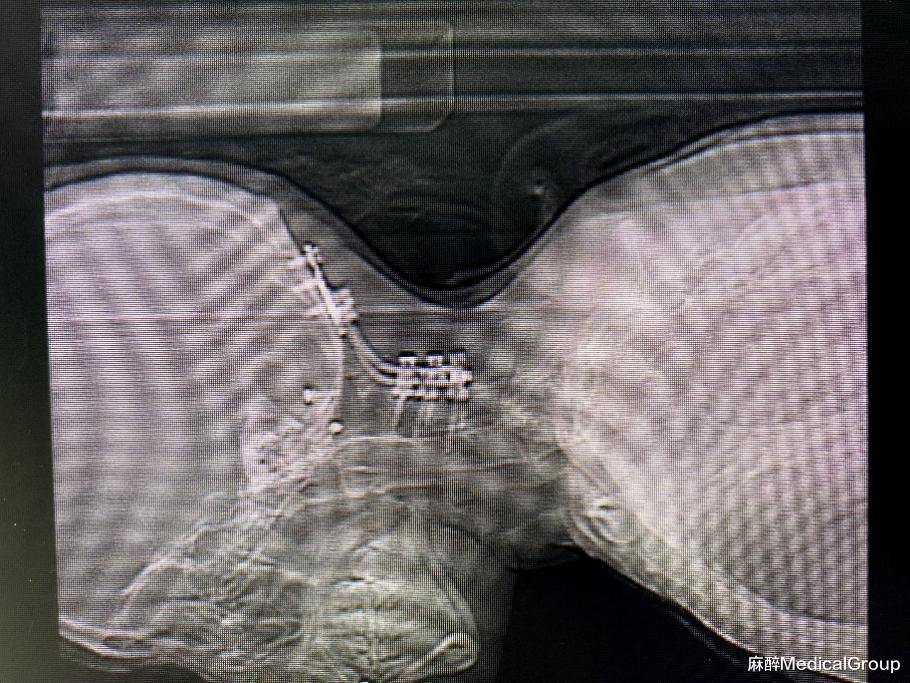

白大姐,43岁,以"甲状腺肿物"入院,拟行:单侧甲状腺切除伴甲状腺峡部切除术。身高仅141cm,且伴有脊柱侧凸畸形,重要的是两年前因为“寰枕交界畸形”行颈2.3.4.5.6.7椎体固定融合术,目前颈部活动受限,屈伸、转动皆困难。马氏分级3级,张口度<4cm,作为麻醉医生,立刻警觉——这是典型的困难气道。

患者入室后→2%利多卡因10ml雾化吸入15分钟(氧流量5L/min)→患者躺平后给予预吸氧5分钟→8%七氟烷、氧流量8L/min面罩吸入1~2分钟(此时患者意识模糊、嗜睡、呼吸浅慢)→开始操作,纤支镜顺利过会厌,进入声门,看见隆突,置入气管导管。患者整个过程患者无烦躁与呛咳,导管置入后患者睁开眼睛,可眨眼配合,心率血压无剧烈波动,插管顺利。接着静注丙泊酚、瑞芬、罗库后改为机械通气。注:每个患者耐受程度有区别,耐受差的可以追加表麻,操作纤支镜在舌根、软腭、咽喉或气管内喷少许利多卡因进行强化。